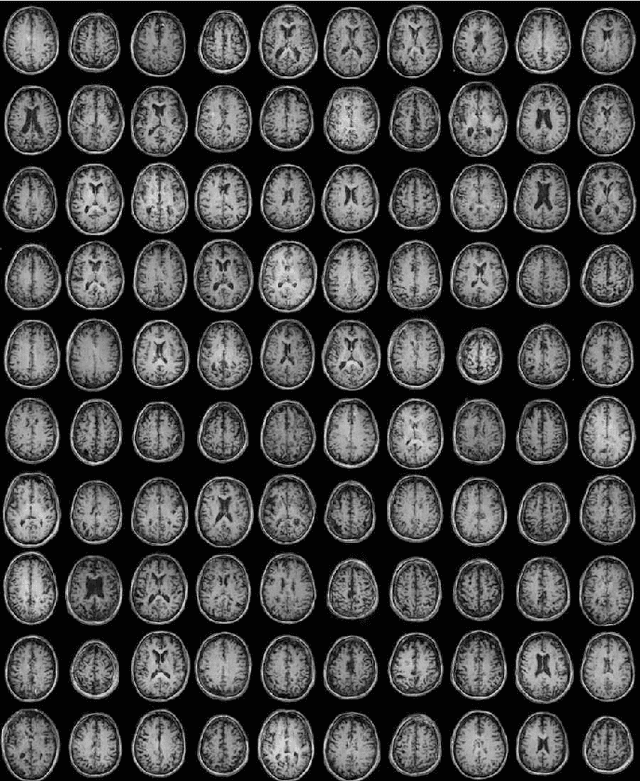

Abstract:Blind harmonization has emerged as a promising technique for MR image harmonization to achieve scale-invariant representations, requiring only target domain data (i.e., no source domain data necessary). However, existing methods face limitations such as inter-slice heterogeneity in 3D, moderate image quality, and limited performance for a large domain gap. To address these challenges, we introduce BlindHarmonyDiff, a novel blind 3D harmonization framework that leverages an edge-to-image model tailored specifically to harmonization. Our framework employs a 3D rectified flow trained on target domain images to reconstruct the original image from an edge map, then yielding a harmonized image from the edge of a source domain image. We propose multi-stride patch training for efficient 3D training and a refinement module for robust inference by suppressing hallucination. Extensive experiments demonstrate that BlindHarmonyDiff outperforms prior arts by harmonizing diverse source domain images to the target domain, achieving higher correspondence to the target domain characteristics. Downstream task-based quality assessments such as tissue segmentation and age prediction on diverse MR scanners further confirm the effectiveness of our approach and demonstrate the capability of our robust and generalizable blind harmonization.

Abstract:In MRI, images of the same contrast (e.g., T1) from the same subject can show noticeable differences when acquired using different hardware, sequences, or scan parameters. These differences in images create a domain gap that needs to be bridged by a step called image harmonization, in order to process the images successfully using conventional or deep learning-based image analysis (e.g., segmentation). Several methods, including deep learning-based approaches, have been proposed to achieve image harmonization. However, they often require datasets of multiple characteristics for deep learning training and may still be unsuccessful when applied to images of an unseen domain. To address this limitation, we propose a novel concept called "Blind Harmonization," which utilizes only target domain data for training but still has the capability of harmonizing unseen domain images. For the implementation of Blind Harmonization, we developed BlindHarmony using an unconditional flow model trained on target domain data. The harmonized image is optimized to have a correlation with the input source domain image while ensuring that the latent vector of the flow model is close to the center of the Gaussian. BlindHarmony was evaluated using simulated and real datasets and compared with conventional methods. BlindHarmony achieved a noticeable performance in both datasets, highlighting its potential for future use in clinical settings.